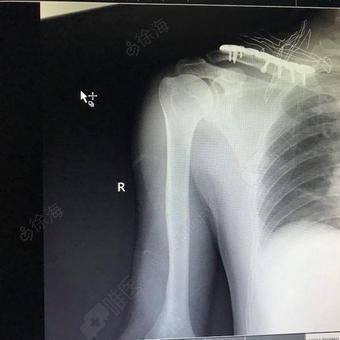

右侧锁骨骨折(恒扬)

右锁骨骨折

右侧锁骨骨折